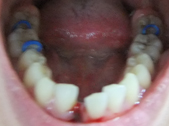

把图缩小了,还是一样惊人!被吓到的朋友真的对不起了! 下牙中间冒血的位置就是牙齿原来所在的地方啦~后面蓝色的就是橡筋,这几根橡筋威力比拔牙更大!!痛死了!!